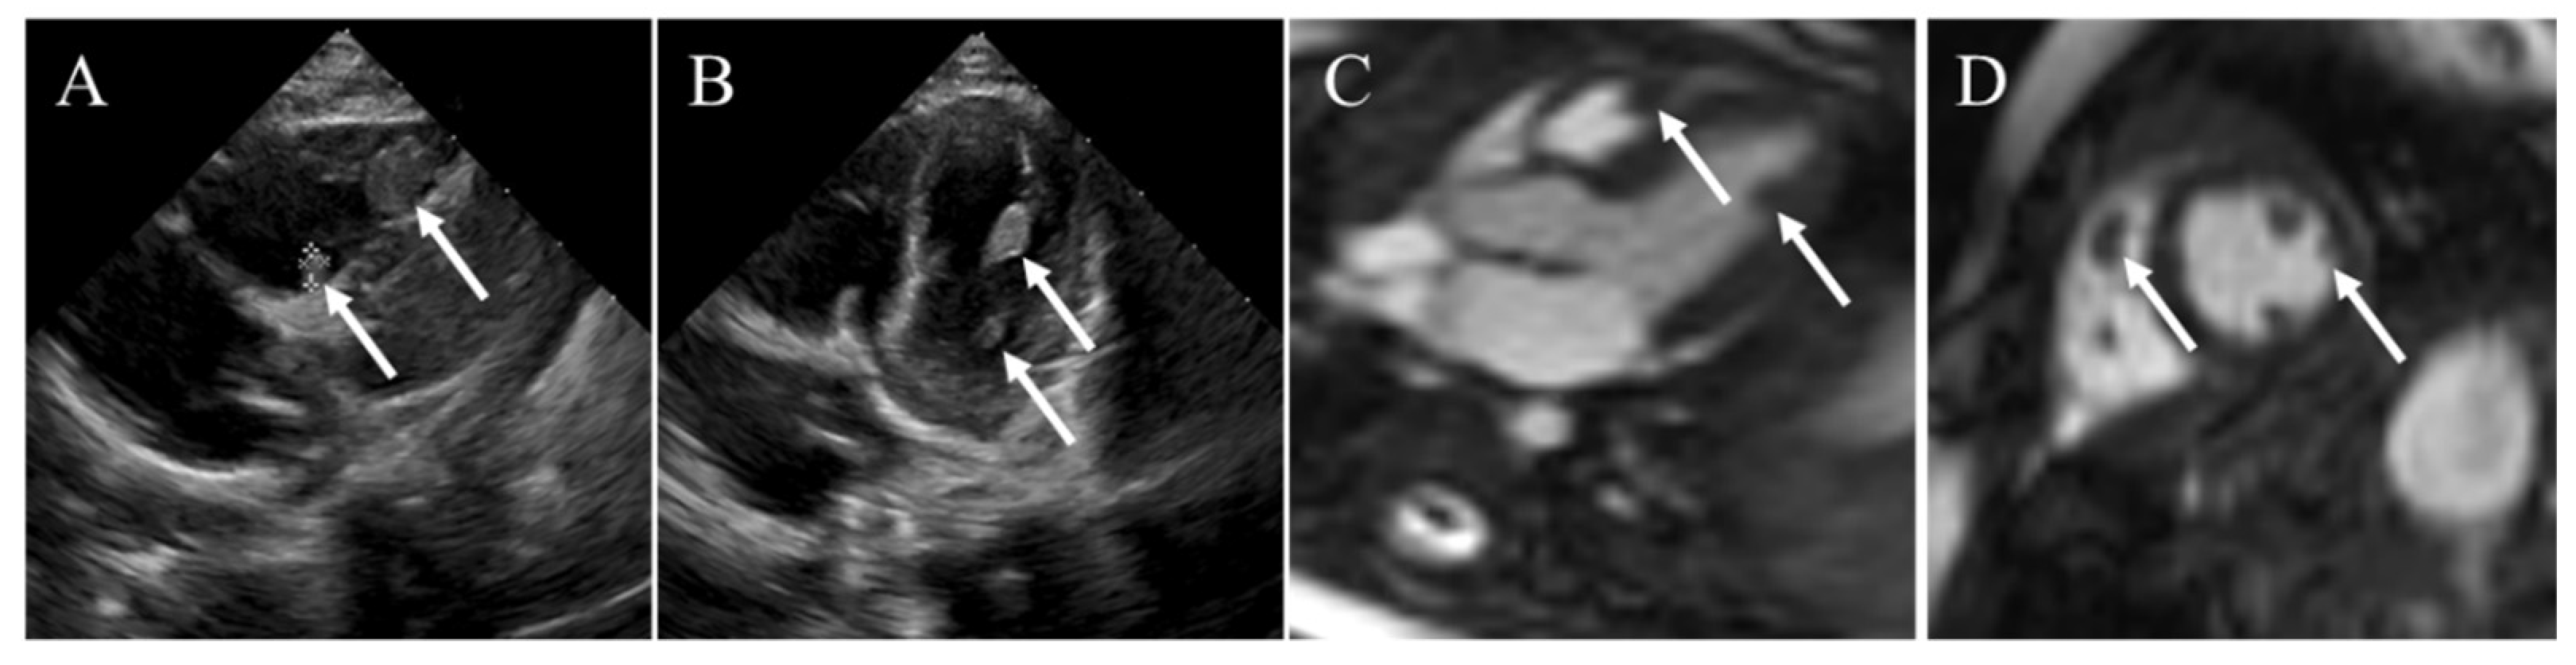

4.4. Rhabdomyoma

| Rhabdomyoma | Infants and children | No defined sex distribution | Usually intramyocardial or intracavitary; no difference in distribution between the left and right heart | Multiple; small; round; lobulated; well-circumscribed; homogenous hyperecho | Multiple homogeneous low attenuation; no enhancement | Isointense on T1WI; hyperintense on T2WI; no enhancement |

- Ganame, J.; D’Hooge, J.; Mertens, L. Different deformation patterns in intracardiac tumors. Eur. J. Echocardiogr. 2005, 6, 461–464. [Google Scholar] [CrossRef]